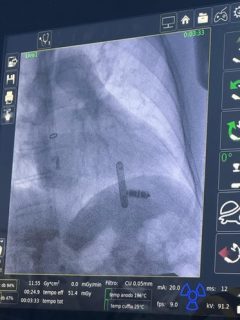

Primo impianto di pacemaker senza fili per via giugulare in Sardegna

È passato un altro anno nella Cardiologia dell’ospedale Nostra Signora di Bonaria di San Gavino ma la voglia d’innovare per offrire ai pazienti i migliori standard di cura non è cambiata. Il reparto diretto dalla dottoressa Maria Valeria Demontis prosegue nel percorso tracciato già dal 2016 dal dottor Gianfranco Delogu, recentemente andato in pensione, e inizia l’anno con alcune innovative procedure di cardiostimolazione. In particolare, a metà febbraio il reparto del Medio Campidano è stato il teatro del primo impianto in Sardegna di pacemaker leadless (senza fili) non col classico approccio venoso dall’inguine ma tramite venga giugulare destra.

Questa tecnica, presentata solo l’anno scorso con uno studio di confronto nella prestigiosa rivista Europace, risulta oggi appannaggio di alcuni centri d’élite in Europa ma sta progressivamente prendendo piede anche in Italia. L’acquisizione di un accesso venoso tramite le vene del collo presenta notevoli vantaggi come la minore durata dell’intervento e dell’esposizione radiologica, una percentuale di complicanze fino a cinque volte inferiori rispetto all’approccio femorale e dei tempi di recupero del paziente molto brevi.

“L’introduzione di modalità d’impianto più rapide e sicure per dei dispositivi che sono dei gioielli di tecnologia favorisce l’utilizzo di questi anche in pazienti fragili e con scarso patrimonio vascolare a livello femorale, via tradizionalmente utilizzata negli anni passati ma gravata di un rischio di complicanze superiore”, sostiene il dottor Roberto Floris, aritmologo interventista che ha eseguito la procedura con elevata competenza e professionalità, frutto del suo costante impegno, aggiornamento continuo e dedizione all’interventistica. “Questa tecnica necessita di un accesso venoso giugulare ecoguidato e permette una minore invasività, inoltre il paziente potrà assumere la posizione seduta appenda dopo l’impianto e mobilizzarsi dopo solo poche ore, cosa assolutamente impossibile con l’approccio da vena femorale”.